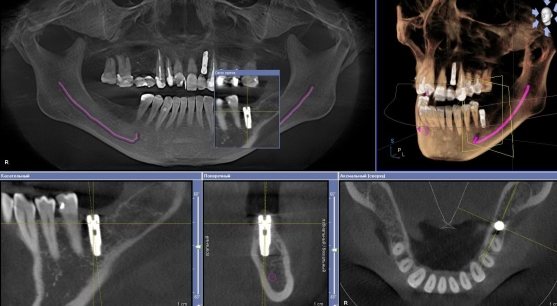

Компьюторная томография (3D-рентген).

На обычном рентгене врач может не увидеть воспаление корня, другие скрытые проблемы, что чревато осложнениями. Для компьютерной томографии практически нет заболеваний или дефектов, которые нельзя рассмотреть. Она позволяет диагностировать даже начальный этап воспаления, предсказать обратимо оно или нет.

Чаще всего КТ применяют в хирургической стоматологии, при планировании операции, имплантации. Некоторые томографы оснащены программами рекомендующими, куда лучше поставить имплантат с базами данных их размеров, форм.

Трехмерное изображение позволяет просматривать челюсти со всех сторон, видеть все недостатки корневой системы, выбирать оптимальную отправную точку для операции. Точность диагностики значительно выше, в большинстве случаев отпадает необходимость других исследований – все видно на мониторе. Томографию можно делать много раз подряд, наблюдать за изменениями до и после лечения.

На заметку: показания для КТ в стоматологии — необходимость точной диагностики в любой сфере: имплантологии, терапии, хирургии, ортодонтии, ортопедии.